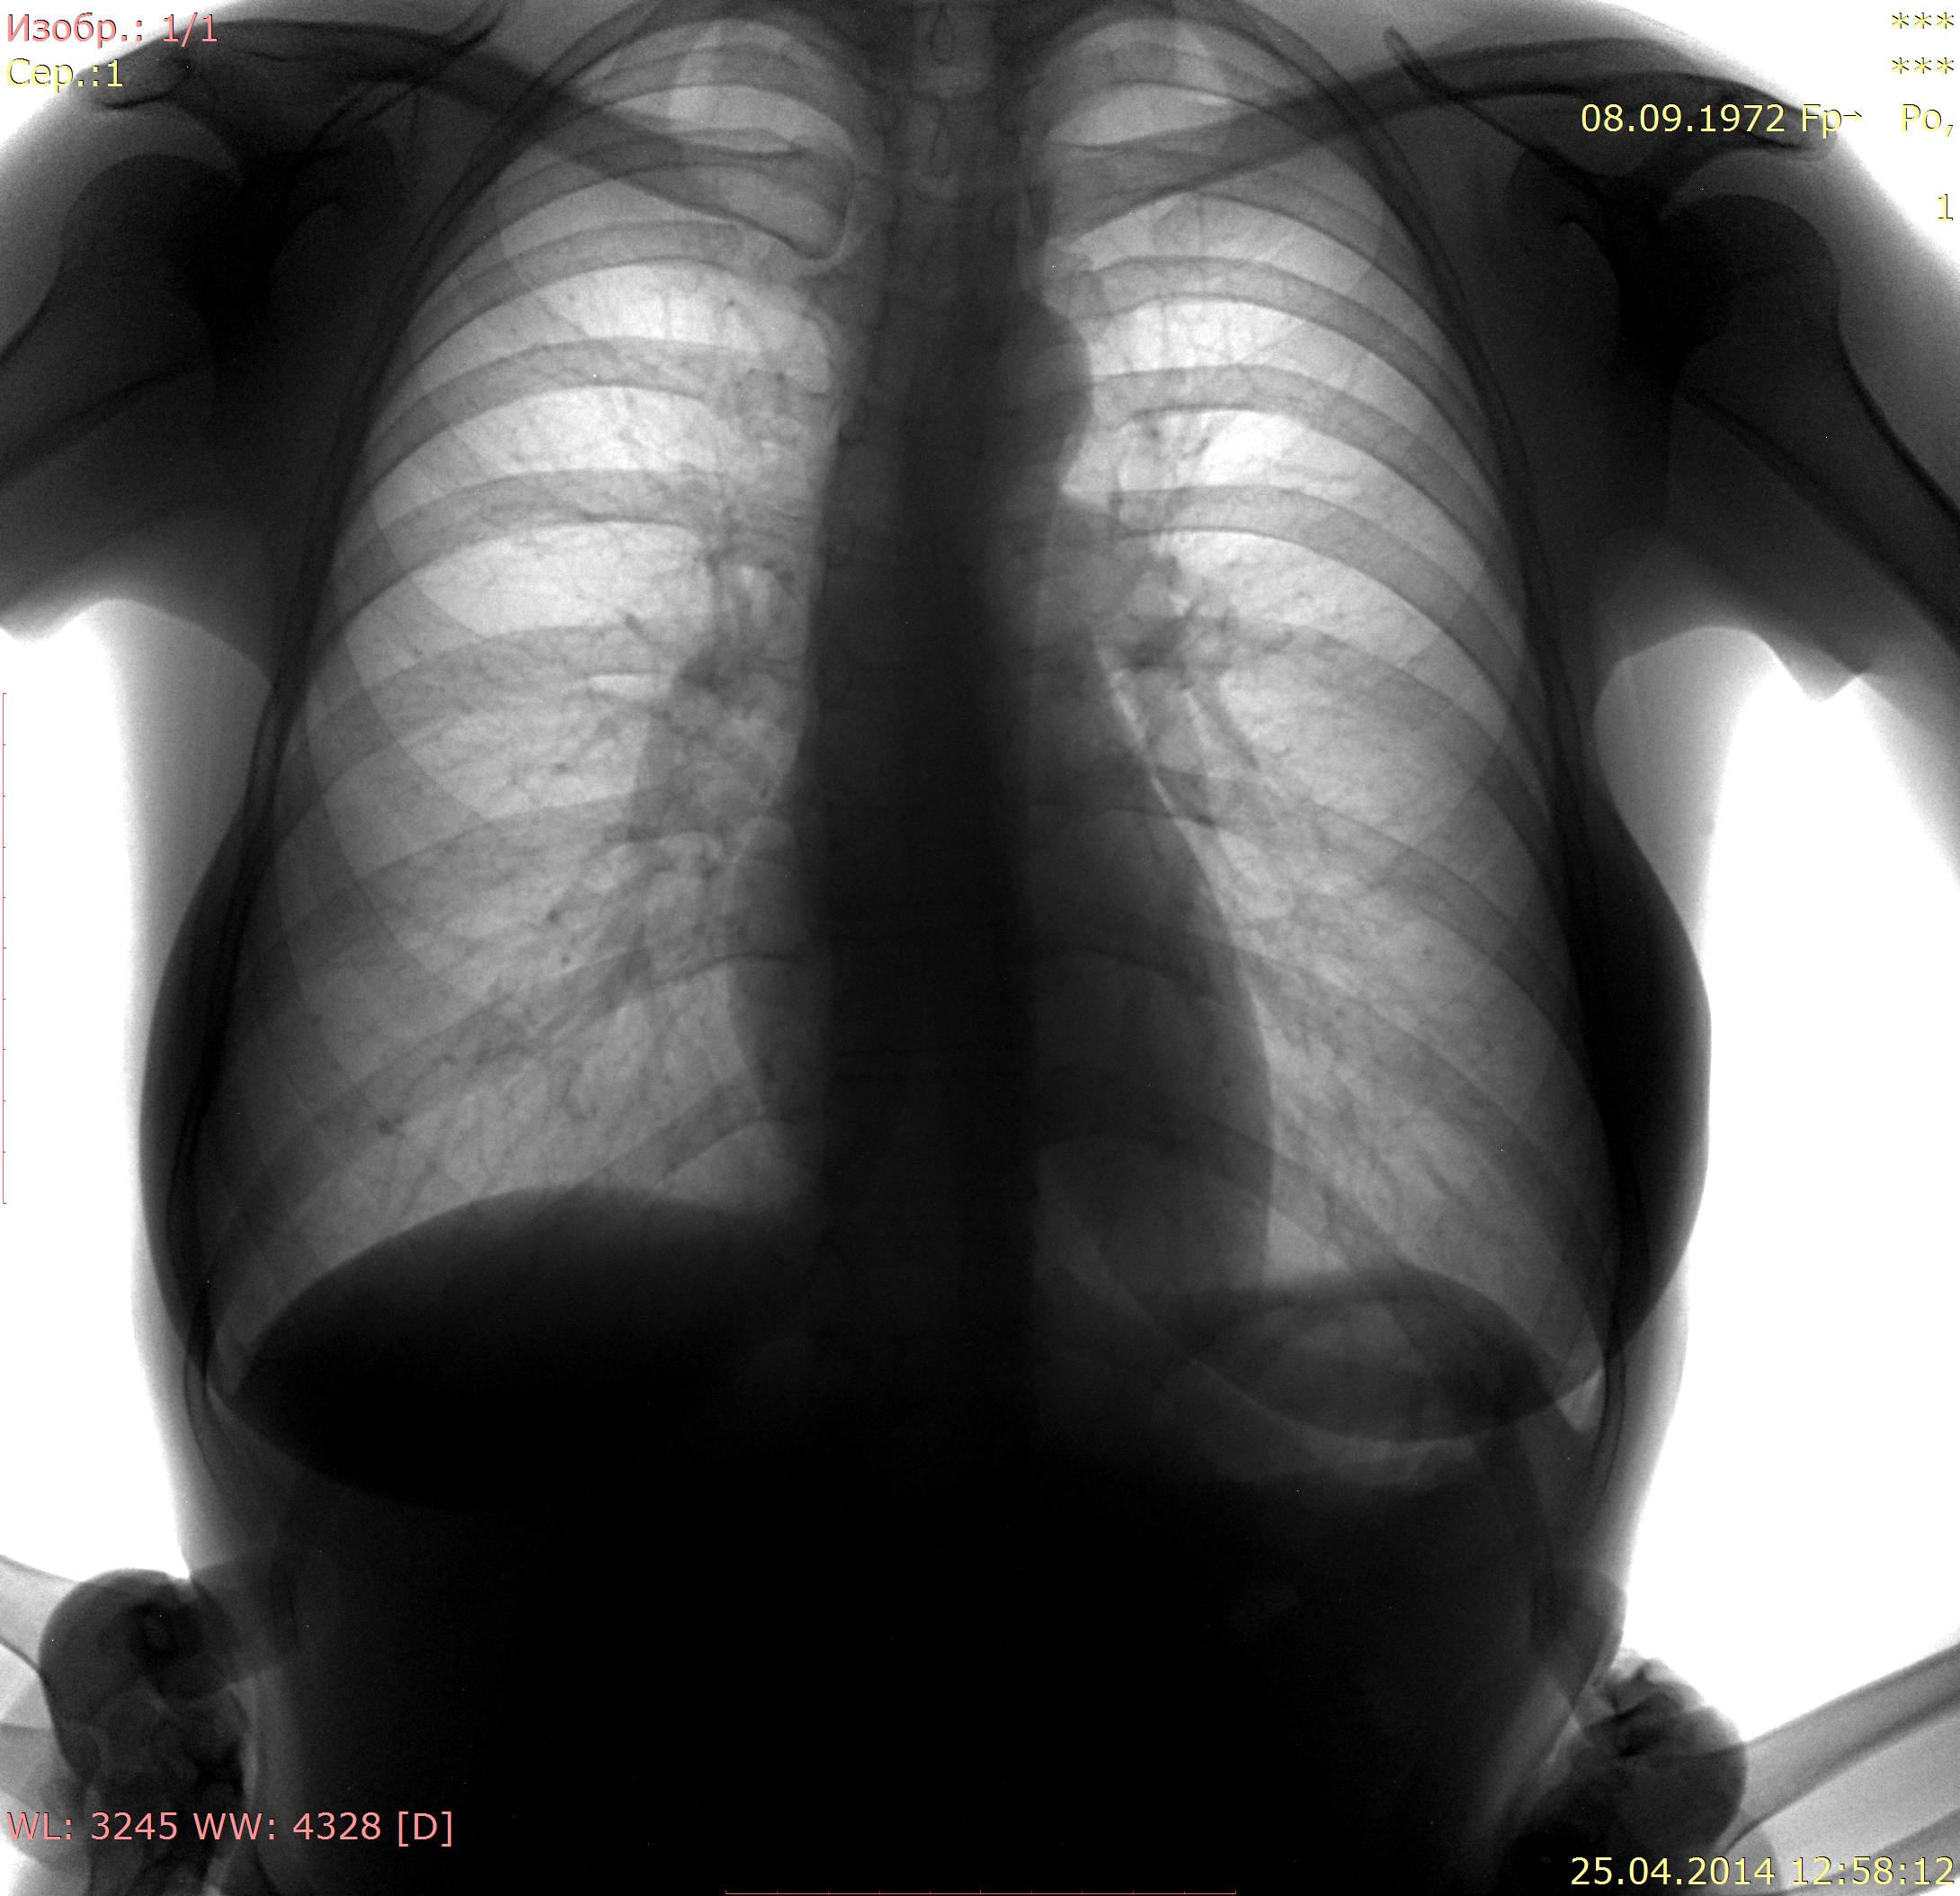

Пересняли

Теперь ничего криминального не вижу. Пусть живёт долго и счастливо!

Норма.

Все равно кажется тонкостенная воздушная полость есть-но тут глубокое ИМХО.Сосудистый рисунок, видимо. Но на боковой тоже есть.Очень ИМХО. Но и с этим можно жить долго и счастливо.Не будем придираться.

На втором снимке, в отличие от первого, задний отрезок 4-го ребра справа расположен выше ключицы, а на первом снимке - на ключице. На втором снимке наружные синусы больше прикрыты тенями молочных желез, на первом снимке - меньше. Значит центральный луч при съёмке во втором случае располагался выше, чем в первом случае, и видимая на первом снимке тень на втором сместилась книзу. Потеряла четкость, располагается там же, на 6-м ребре, но ниже. И все равно линия сосудистого рисунка здесь как бы замыкает овал.